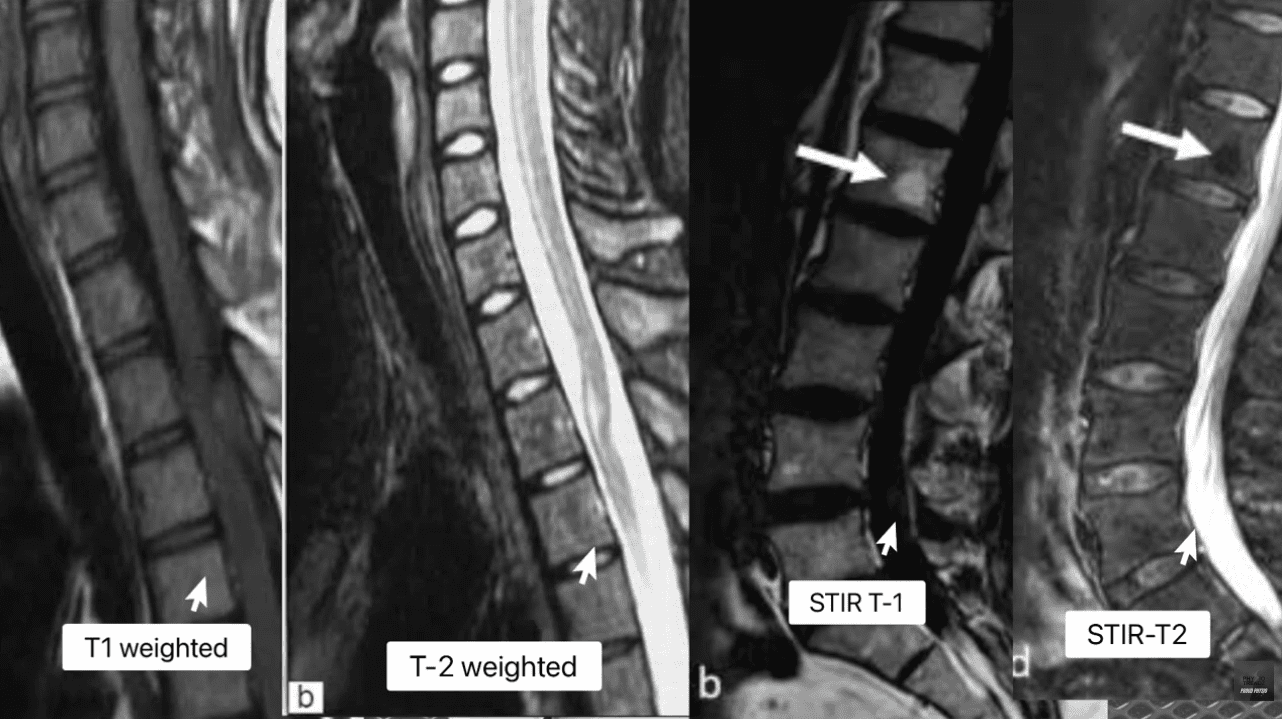

My method for forensic MRI interpretation depends on a nuanced understanding of various pulse sequences and their physiological meaning (Advanced MRI Interpretation, n.d.). I meticulously review the T1-weighted, T2-weighted, and Short Tau Inversion Recovery (STIR) sequences because they tell different stories about the underlying tissue pathology.

STIR (Fat-Suppressed) Water (Edema, CSF, Inflammation) Fat (Marrow) Acuity: The definitive sequence for acute trauma. By suppressing fat signal, any remaining bright signal is unequivocally edema, confirming acute inflammation in bone or soft tissue.

The presence of edema (abnormal fluid accumulation) in the bone marrow or soft tissues surrounding the spine is, in my professional opinion, the most powerful, objective indicator of acute trauma. This edema is the body’s immediate inflammatory response to injury and provides the temporal signature required for my precise injury dating.

• Modic Type 1 (MC1) – The Acute Signature: MC1 represents the acute inflammatory stage characterized by bone marrow edema. When I see this, I know I’m looking at an injury that is active and recent.

• My Staging: I stage this based on the specific signal patterns: Dark on T1 and Bright on T2/STIR (Spinal Diagnostics, n.d.). The persistent bright signal on STIR is the definitive confirmation of active, acute inflammation.

• My Testimony: I explain to attorneys that MC1 changes typically resolve or transition to the fatty Type 2 changes within approximately 6 to 8 weeks (Spinal Diagnostics, n.d.). Therefore, the presence of MC1 is a powerful, objective sign of recent trauma, often correlating directly with the patient’s reported high pain scores (Jensen et al., 2024). When a defense expert attempts to argue degeneration, my documentation of MC1 provides the irrefutable evidence of a specific, new acute event.

• My Staging: I stage this based on the characteristic Bright on T1/T2 but crucially, Dark on STIR (fat-suppressed) sequence (Spinal Diagnostics, n.d.).